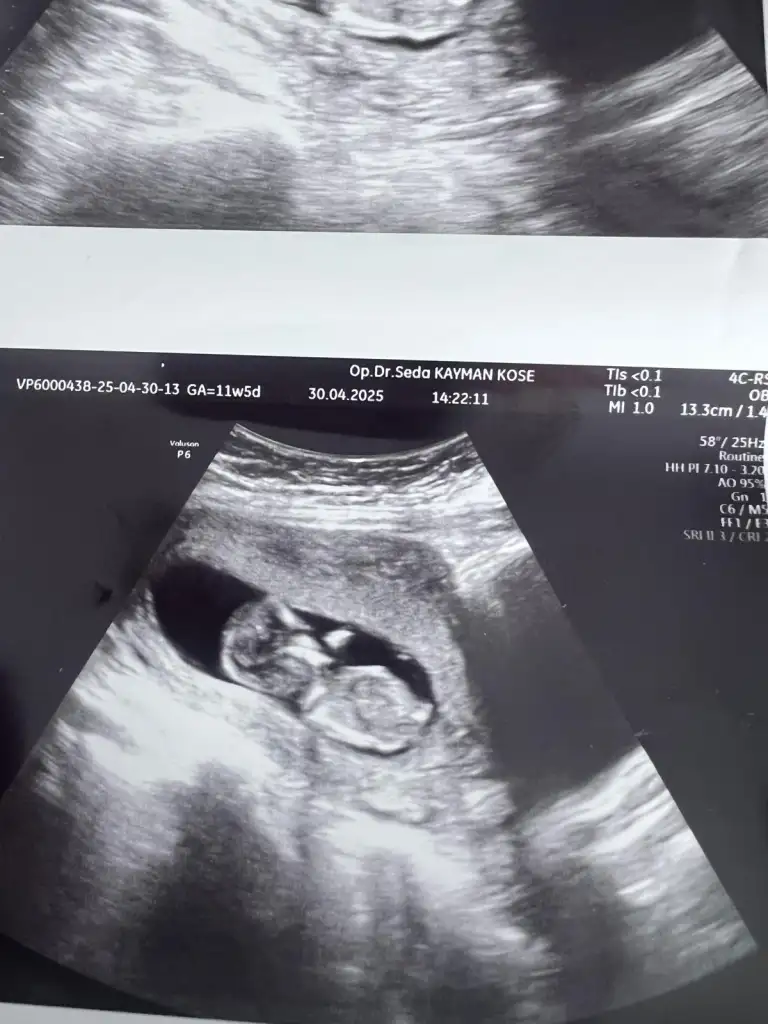

Benim içinde yorum yapabilirmisiniz arkadaşlar ilki 5.5haftalik ikincisi 12.haftalik...

Eklentiler

• 20250422_181122.webp

14 KB · Görüntüleme: 69

• 20250422_053619.webp

13,3 KB · Görüntüleme: 66